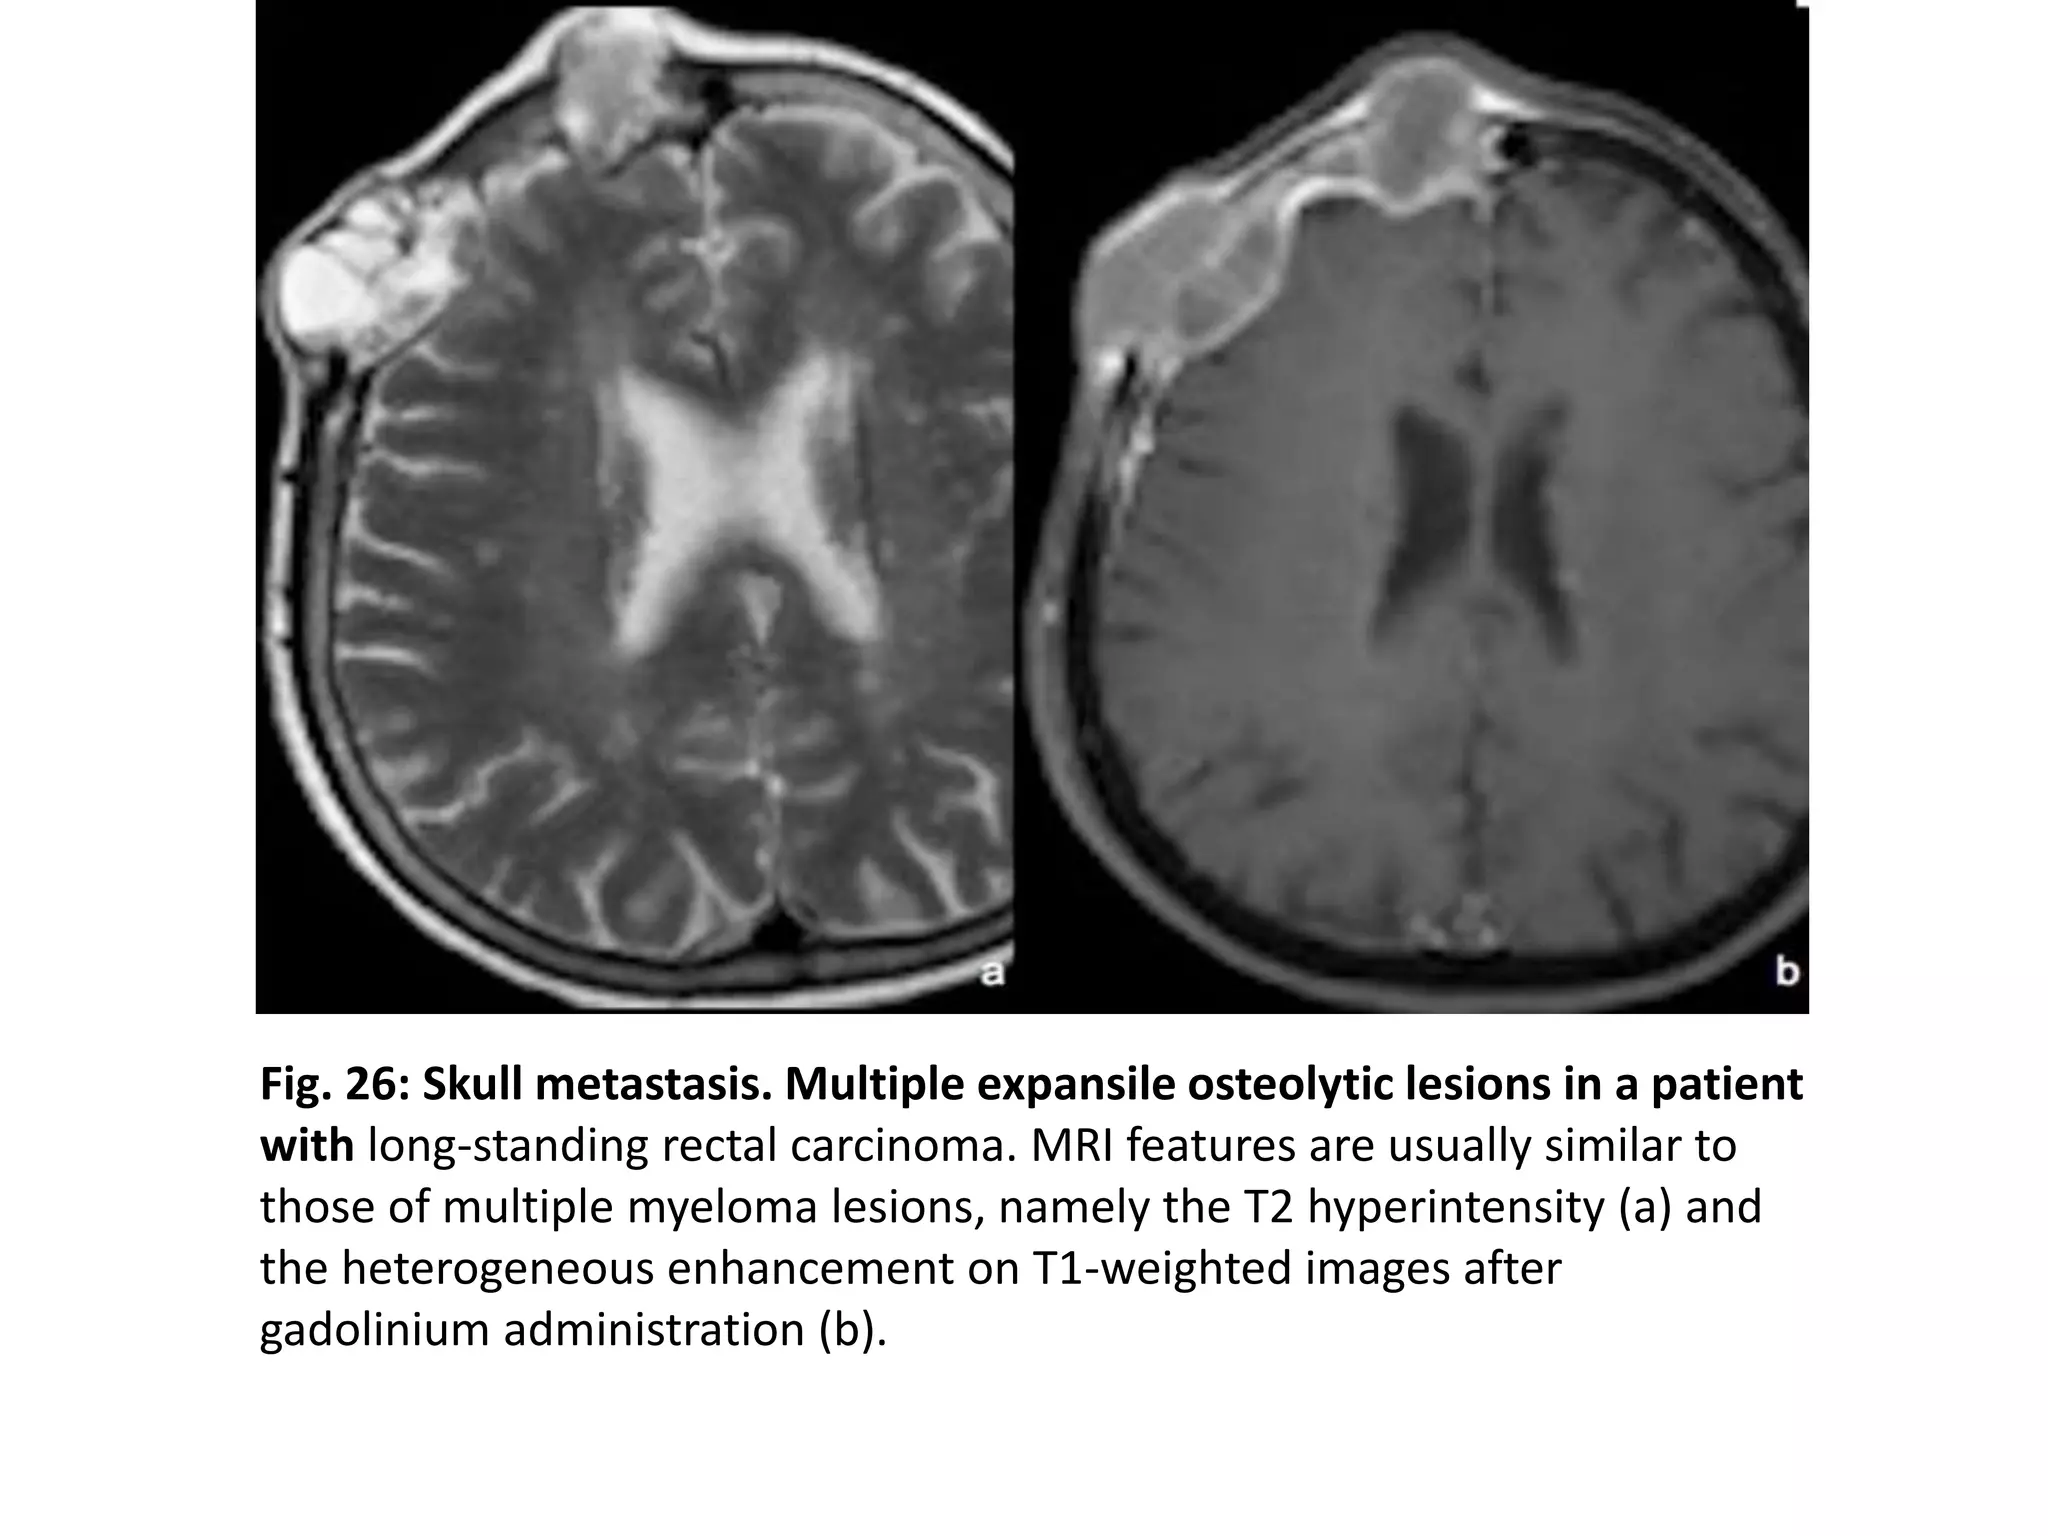

Fig. 26: Skull metastasis. Multiple expansile osteolytic lesions in a patient

with long-standing rectal carcinoma. MRI features are usually similar to

those of multiple myeloma lesions, namely the T2 hyperintensity (a) and

the heterogeneous enhancement on T1-weighted images after

gadolinium administration (b).